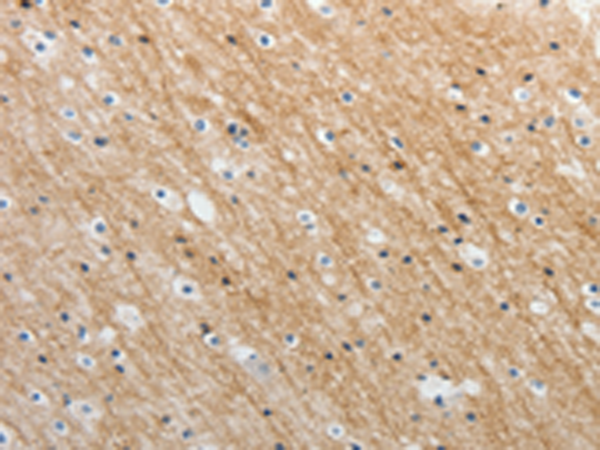

分类: 科研抗体货号: P04218别名: TCF-1应用: IHC反应种属: Human, Mouse